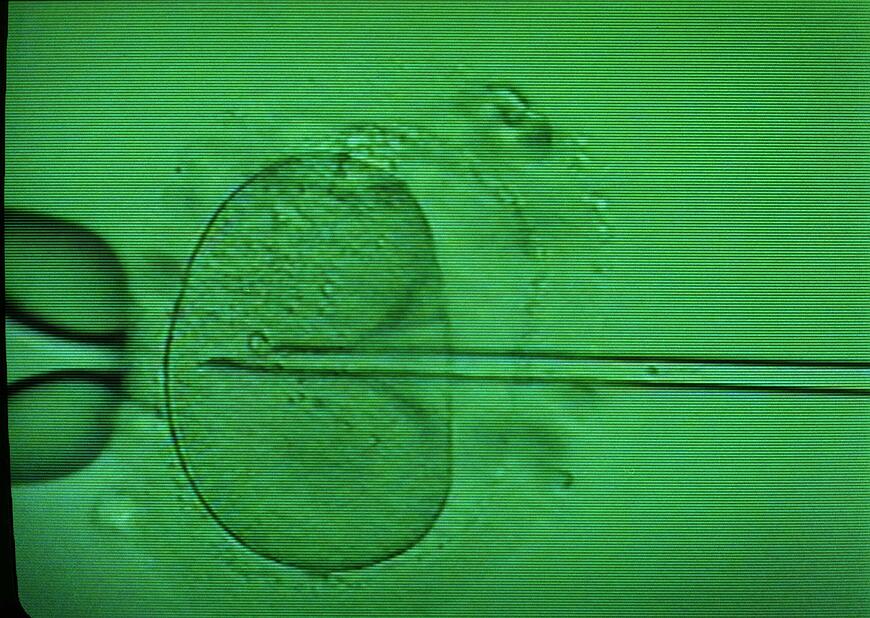

Die „Kultur des Todes“ schlägt um sich. Wieder einmal. Paare, die sich einer künstlichen Befruchtung unterziehen, sollen nach Ansicht der Nationalen Akademie der Wissenschaften Leopoldina die dabei erzeugten und für „überzählig“ erachteten Embryonen künftig der Forschung „spenden“ können. Statt embryonale Stammzellen weiter aus dem Ausland zu importieren, sollten deutsche Forscher diese demnächst selbst aus „überzähligen“ Embryonen isolieren und kultivieren können.

Was die Leopoldina in ihrer, in dieser Woche vorgestellten 55-seitigen Stellungnahme „Neubewertung des Schutzes von In-vitro-Embryonen in Deutschland“ fordert, bedeutet in Summe nicht weniger als den Einstieg Deutschlands in die embryonenverbrauchende Forschung.